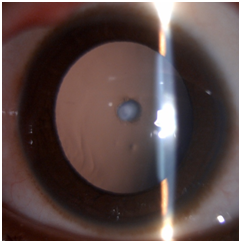

Intraoperative challenges in paediatric cataract surgery are running off capsulorhexis due to elasticity of the capsule, positive intravitreal pressure, intraoperative miosis and wound leak. These complications have significantly reduced using closed chamber surgical technique. Postoperative complications include uveitis, posterior capsule opacification, glaucoma, pupillary capture and retinal detachment. Visual axis opacification (VAO) is the most common complication after a successful cataract surgery in children. The PCO is amblyogenic and the purpose of surgery is defeated if long-term clear visual axis is not achieved. A child’s eye tends to show more tissue reaction than an adult. The inflammatory response can be managed with the use of intensive topical steroid tapered over a period of 6 to 8 weeks. Topical antibiotics are instilled for two weeks and cycloplegic eye drops for four weeks to prevent posterior synechiae formation. Refraction should be done as soon as inflammation subsides and appropriate correction with aphakic glasses, contact lenses or bifocals should be provided based on the age of the child (Figures 1–5).

Figure 2 Anterior Polar cataract.